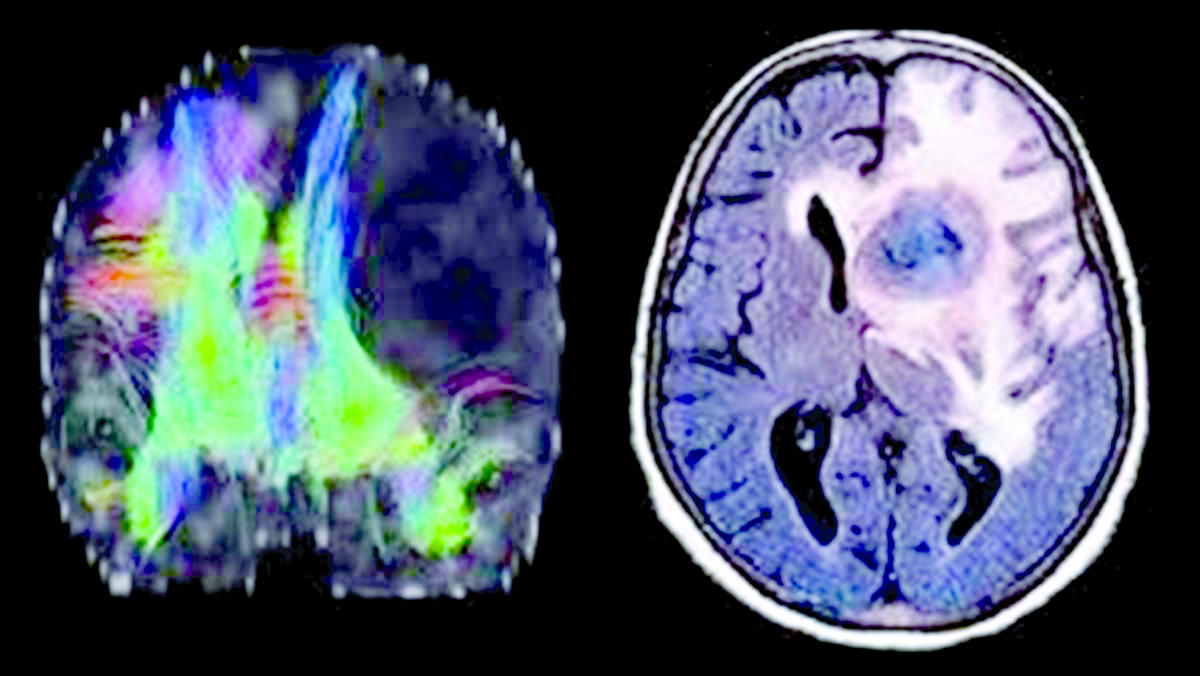

طور علماء أمريكيون جهازا لاسلكيا يزرع بين الجلد والجمجمة يمكنه قتل أورام الدماغ الفتاكة، وإنقاذ حياة العديد من المرضى المصابين بسرطان الدماغ، الذي يعد أحد أكثر أشكال المرض خطورة.

وقام الخبراء بزراعة الجهاز الذي به غرسة الدماغ الجديدة بين الجلد والجمجمة، التي تم تنشيطها عن بعد، بتسخين جزيئات الذهب النانوية التي تحتويها، لقتل السرطان من الداخل، وهي عملية يمكن إجراؤها لمدة 15 دقيقة على مدى 15 يوما فقط، دون الحاجة إلى التدخل الجراحي.

كما أن هذا الابتكار الذي تم تطويره يزيد درجة الحرارة بما يصل إلى 40 درجة فهرنهايت، وهي الدرجة الكافية لقتل الخلايا السرطانية دون الإضرار بأنسجة المخ المحيطة، وعلى الرغم أنه في الوقت الحالي يتم اعتماد تقنية استخدام الحرارة، التي تسمى المعالجة الحرارية الضوئية، لعلاج الأورام، لكنها لم تكن ممكنة إلا أثناء الجراحة.